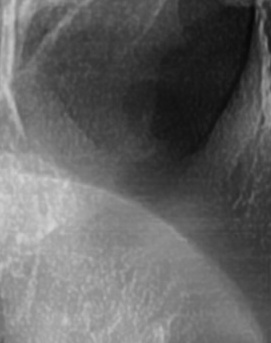

어금니 뒤 잇몸 부음 우선 원인부터 살펴보면 이러한 증상은 단순한 잇몸 염증에서부터 더 심각한 치주 질환이나 사랑니 문제까지 다양하게 발생할 수 있는데요. 보통 잇몸이 붓는 것은 세균 감염, 음식물 잔여물에 의한 자극, 치주 질환, 사랑니 문제 등이 원인이 되는 경우가 많으며 증상이 가벼울 때는 자연적으로 가라앉을 수도 있지만, 제대로 치료하지 않고 반복되는 잇몸 문제가 갈수록 진행된다면 염증이 심해지고 통증이 심해질 수 있고 잇몸이 주저 앉거나 심한 경우 치아가 흔들릴 수 있어서 원인을 정확하게 파악하고 적절한 치료를 받는 것이 중요하다고 볼 수 있어요

좀더 자세히 원인과 증상에 대해 살펴보면 어금니 뒤쪽은 치아 구조상 칫솔이 잘 닿지 않는 부위라서 음식물 찌꺼기가 남아 있거나 플라그가 쉽게 쌓이게 되는데 치아 사이 공간이 좁고 잇몸이 연약한 부분이라서 세균이 번식하기 쉬운 환경이 만들어지고, 이로 인해 잇몸이 붓거나 염증이 생길 가능성이 커질 수 있었어요

처음에는 가볍게 붓고 불편한 정도지만, 점점 심해지면 통증이 발생하거나, 잇몸이 붉어지고 단단해지면서 눌렀을 때 고름이 나오는 경우도 있어요. 이런 경우 단순한 염증이 아니라 치주염으로 발전할 가능성이 있기 때문에 치과에서 정확한 검진을 받는 것이 필요한 거예요